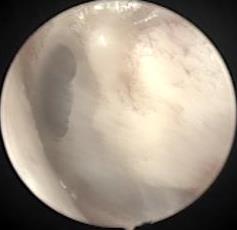

• 耳内镜下耳屏软骨-软骨膜鼓膜修补术后的短期疗效观察

摘要:目的 探讨耳内镜下耳屏软骨-软骨膜鼓膜修补术后的短期疗效。方法 回顾性分析2019年9月-2022年8月该院收治的78例鼓膜穿孔患者的临床资料,患者均采用耳内镜下鼓膜修补术。术后随访3个月,观察鼓膜形态和穿孔愈合情况,记录内镜图像、干耳时间、术前术后听力及耳鸣情况,以及外耳道狭窄等并发症的发生率。结果 术后3个月,鼓膜穿孔愈合率为97.44%(76/78),愈合良好,平均气导听阈较术前明显改善,气骨导间距较术前明显缩小,耳鸣较术前明显改善,差异均有统计学意义(P<0.05)。干耳时间为(4.21±1.12)周。术后出现肉芽5例,再穿孔2例,真菌感染2例,术腔感染、耳屏感染、外耳道狭窄和切口瘢痕各1例,所有患者术后均未发生面神经麻痹和感音神经性聋等严重并发症。结论 耳内镜下耳屏软骨-软骨膜鼓膜修补术是一种安全、有效的手术方法。根据术后愈合规律、内镜下鼓膜和外耳道形态特征,可为鼓膜修补术后正常中耳转归和并发症的诊疗,提供临床参考。